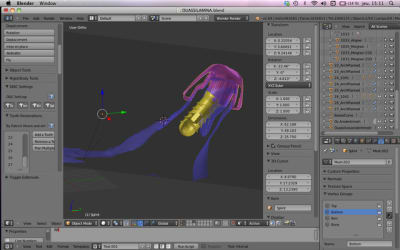

Je n'ai plus la collision dans le hardware .

Comment fait on pour passer de install implant mode en object mode ?

Par contre j'ai un probleme pour lier le cylindre guide sur la base . Apparement tu as eu aussi ce probleme mais je n'ai pas compris la solution que tu as mise en oeuvre

lors du 1er essai tu as un message d'erreur

ensuite tu cliques sur la petite clé de la barre d'outil

et tu cliques sur la croix

cela fonctionne quand tu recommences !